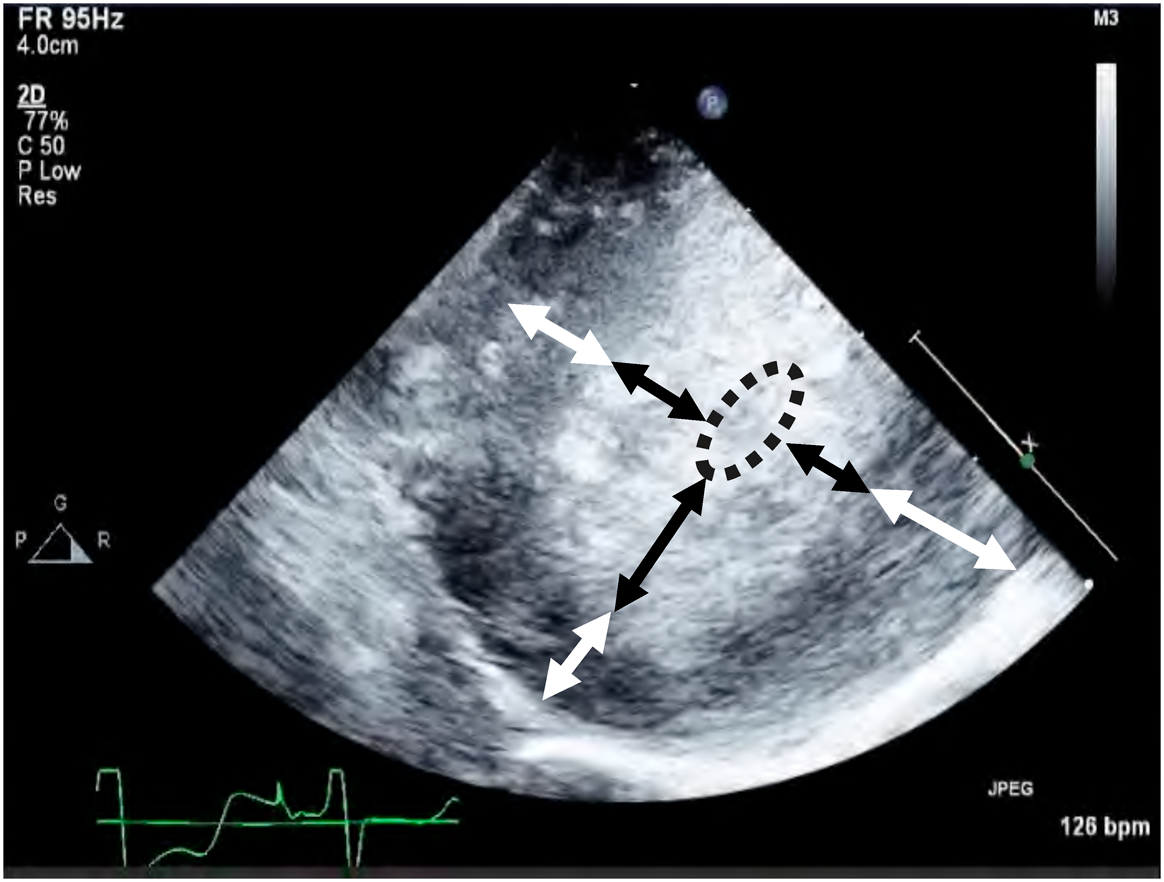

Intracardiac repair was completed within 136 minutes of cardiac arrest. Off cardiopulmonary bypass was attempted but infeasible. Blood pressure could not be maintained even with a large amount of inotropic support and additional volume infusion. After these interventions, epicardial echocardiography showed severely thickened LV wall and a nearly empty intraventricular cavity during attempted weaning from cardiopulmonary bypass (Fig. 1), probably due to adverse effect of long aortic cross-clamp time. No LV output was observed, and the aortic valve was non-functional. The patient was therefore placed on ECMO.